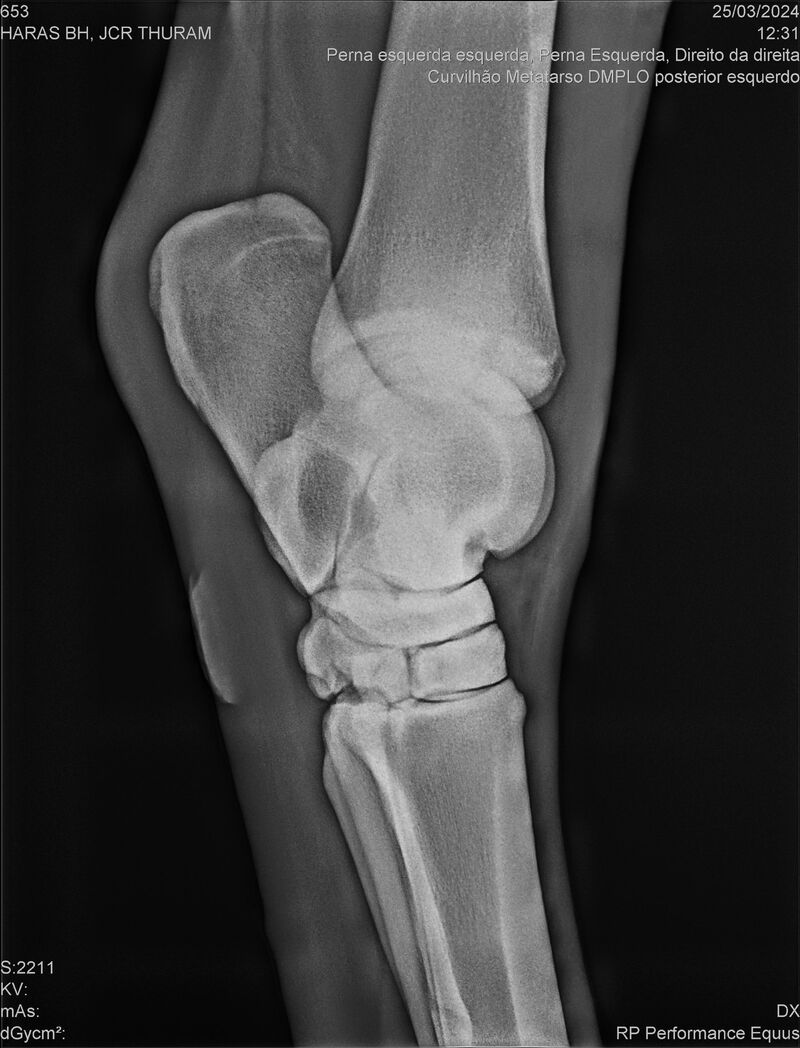

JCR THURAM

Raça: BRASILEIRO DE HIPISMO

Sexo: CASTRADO - CASTRADO

Nascimento: 10/01/2021

Registro: 27531-BH

Vend.: HARAS BH